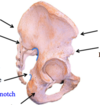

Pelvic Brim

Coccyx

Sacrum

Os coxae

Ilium

Acetabulum

Ischium

Pubis

Posterior/Anterior, Superior/Inferior Iliac Spines

Greater sciatic notch

Ischial spine

Lesser sciatic notch

Ischial tuberosity

Iliac Blade

Iliac Crest

Superior pubic ramus

Ischiopubic ramus

Obturator foramen

Pubic symphysis